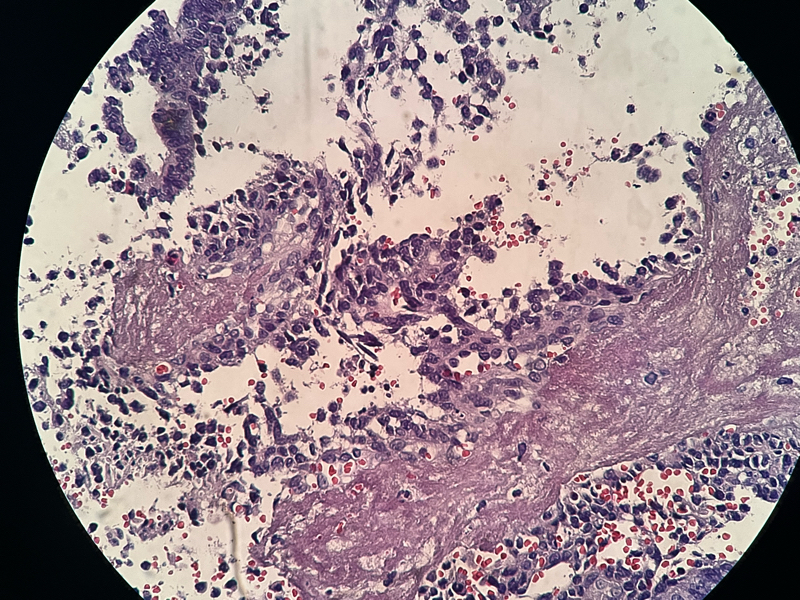

宫内膜组织

性别

女

年龄

37

临床诊断

功血

一般病史

阴道不规则流血20天

标本名称

大体所见

灰白灰红膜样物质一堆,约2.1✖️1.2✖️0.4

倾向内膜息肉

组织形态符合子宫内膜息肉,表面有乳头的那些区域要鉴别乳头样化生和表面浆液性肿瘤,免疫组化可能会有帮助。